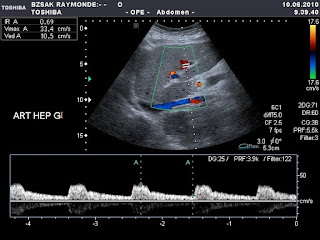

Ennek megfelelo magas RI ertek az a. hepaticaban jobb olodalon

Normalis RI ertek az a. hepatica baloldali fotorzseben

A nem transplantalt majban az arterias RI ertek 0.7 alatt optimalis.